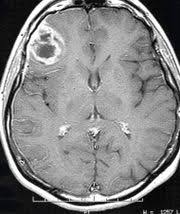

Auch 18 Monate nach der Operation ist der Patient beschwerdefrei ohne neurologische Symptome. Bei unkompliziertem Verlauf und guter Genese können die Patienten nach einer Phase der Erholung nach der Hirn OP die Klinik in etwa 7 bis 10 Tagen wieder verlassen. In der Verlaufskontrolle 3 Monate nach OP berichtete der Patient über Wohlbefinden.

Auch 18 Monate nach der Operation ist der Patient beschwerdefrei ohne neurologische Symptome.